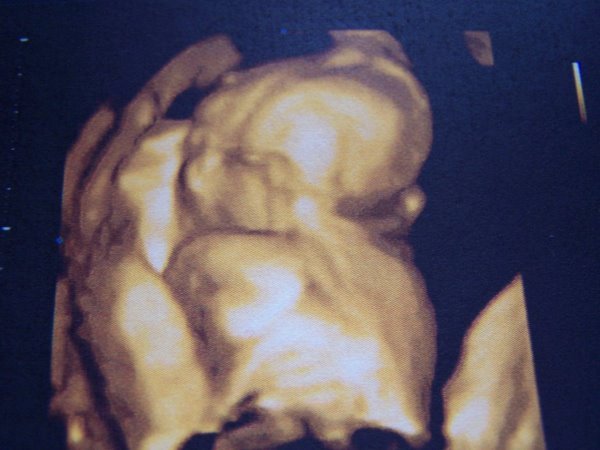

Szabim is mindig kisebb volt, mint Nati, 2 évesen is még 4 cm-rel alacsonyabb. Nem mindenki egyforma, az kb az első 12 hétre jellemző, utána már óriási eltérések lehetnek. Egy másik dolog pedig, hogy az uh amolyan saccra megy. Szabit születése előtt pár órával 2-2,5 kg-ra tippelték és jól beijeszettek. 2800-zal született, ami ugyan nem egy díjbírkózó, de teljesen ok.